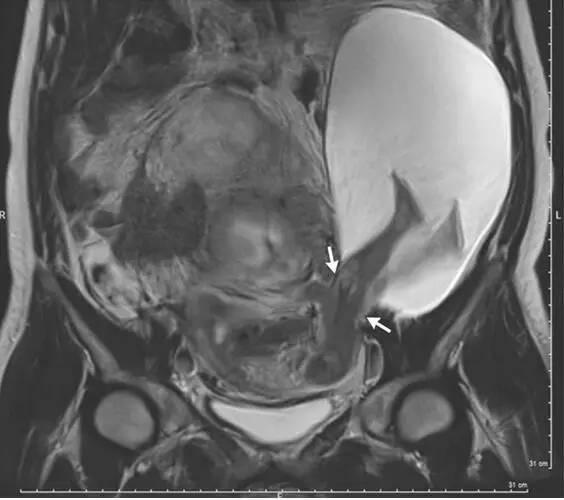

超声波检查显示19×12×9cm的羊膜囊(7.5×4.7×3.5英尺)的一部分通过子宫左壁的一个洞下滑了,胎儿的腿也处于膝盖稍微偏上的位置。MRI扫描显示子宫壁的裂隙扩大到了2.5cm(1英尺)(图中箭头所示)。

在MRI检测2个月之后,也就是怀孕第30周,另一项超声波检查显示这个裂隙的长度已经增加了一倍,到了5cm(2英尺),结果是更多的羊膜囊通过这个缝隙滑了出去,胎儿的身体进去的也更多了,患者的腹部也凸了出来。